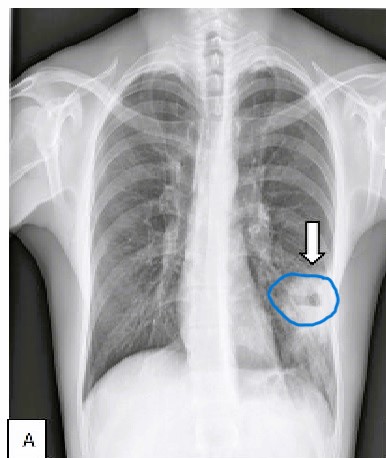

Un abces pulmonar reprezintă o cavitate care se formează în plămân, plină de material purulent, înconjurată de țesut inflamat. De obicei, acesta rezultă din aspirația în plămâni a bacteriilor care trăiesc în faringe sau în cavitatea bucală, în special în șanțul gingival. Abcesul pulmonar poate fi dificil de tratat și poate pune viața în pericol, spun medicii.